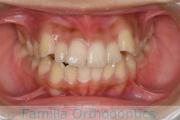

No.22V-449

- 主な症状:

- 上顎前突

- その他の症状:

- 叢生

- 年齢:

- 14歳

- 性別:

- 男性

- 抜歯部位

- 上:

- 44

- 下:

- 8448

- 主な使用装置:

- FEA

- 治療にかかった費用:

- 87万円

歯並びをきれいにしたいということで来院されました。上下左右から小臼歯を抜歯して、マルチブラケット法を行っています。2年弱、25回程度の通院が必要でした。

かなり強い叢生(でこぼこ、凹凸、ガタガタ)ですので、保定をしっかりしないと後戻りのリスクがあります。

- ≫治療前

-

上顎

下顎

前歯の関係など

右側

正面

左側